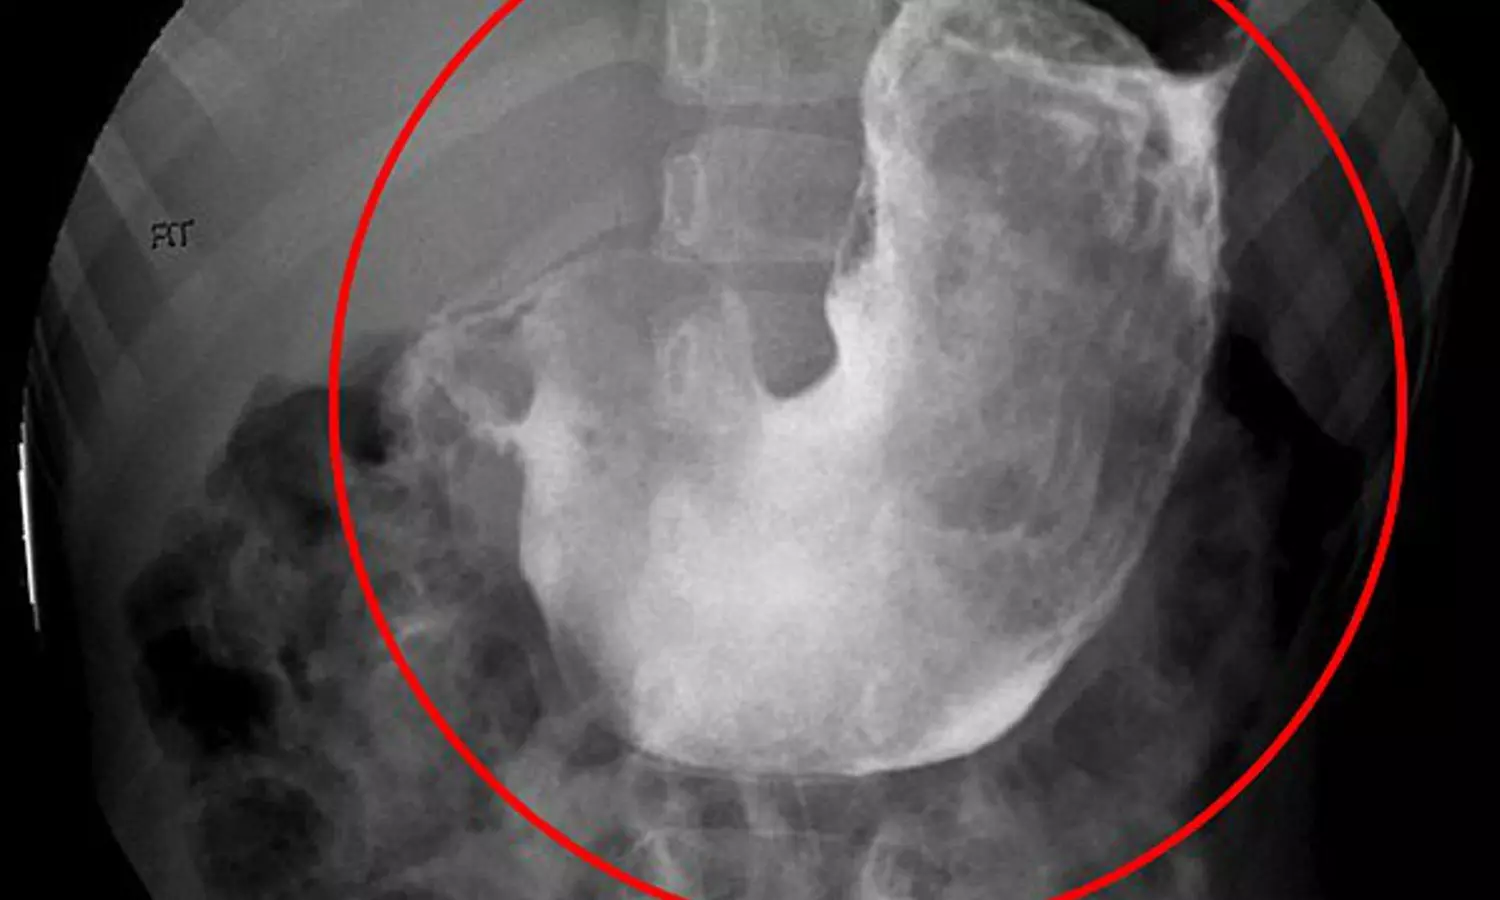

വർഷങ്ങളോളം രോഗ ലക്ഷണങ്ങളൊന്നും കാണിക്കാത്തതിനാൽ തന്നെ വളരെ വൈകിയാണ് രോഗം കണ്ടുപിടിക്കുന്നത്. അപ്പോഴേക്കും മുടി ഒരു ബോളിനോളം വലിപ്പത്തിലായി മാറിയിരിക്കും. അതുകൊണ്ട് തന്നെ ഇത് പുറത്തെടുക്കാൻ ശസ്ത്രക്രിയ ആവശ്യമായി വരുന്നു. ഈയിടെ ചെക്ക് റിപ്പബ്ലിക്കില് പതിനൊന്ന്കാരിയുടെ വയറ്റില് നിന്ന് ഒരു കപ്പോളം വലിപ്പത്തിലുള്ള മുടിക്കെട്ട് പുറത്തെടുത്തിരുന്നു. കഴിഞ്ഞ നവംബറിൽ മുംബൈയിൽ പതിമൂന്ന്കാരിയുടെ വയറ്റിൽ നിന്നും ഒരു കിലോയോളം മുടിയാണ് ഇത്തരത്തിൽ പുറത്തെടുത്തത്.

രോഗം ബാധിച്ചവർ നിരന്തരമായി അവരുടെ തലമുടി കഴിക്കാൻ തുടങ്ങും. ഈ അവസ്ഥയെ ട്രൈക്കോഫാഗിയ എന്ന് പറയുന്നു. ഇത്തരത്തിൽ ധാരാളമായി മുടി കഴിക്കുന്നത് ആമാശയത്തിന്റെ പ്രവർത്തനത്തെ ബാധിക്കുകയും ആരോഗ്യനില വഷളാകാനും കാരണമാകുന്നു. മുടി ദഹിക്കാത്തത് കൊണ്ടുതന്നെ ഇത് മലദ്വാരത്തിലൂടെ പുറത്ത് പോകാതെ കാലക്രമേണ ഇത് വലിയ ഹെയർ ബോൾ ആയി മാറുന്നു. ഒടുവിൽ ദഹന പ്രക്രിയകൾക്ക് തടസ്സമാവുകയും ആരോഗ്യ പ്രശ്നങ്ങൾ നേരിടേണ്ടി വരികയും ചെയ്യുന്നു.

ഹെയർ ബോൾ വളരെയധികം വളരുമ്പോള് ആരോഗ്യപ്രശ്നങ്ങള് കാണിച്ചു തുടങ്ങുന്നു. തുടർന്നു നടത്തുന്ന ടെസ്റ്റിലായിരിക്കും റാപൻസൽ സിൻഡ്രോം ആണെന്ന് കണ്ടെത്തുന്നത്. അപ്പോഴേക്കും കൂടുതൽ പേരിലും ഹെയർ ബോൾ വളരെ അധികം വലുതായിട്ടുണ്ടാവും. അതുകൊണ്ട് തന്നെ ഇത് വായിലൂടെ പുറത്തെടുക്കാൻ സാധിക്കാതെ വരികയും ശസ്ത്രക്രിയ ആവശ്യമാവുകയും ചെയ്യുന്നു.